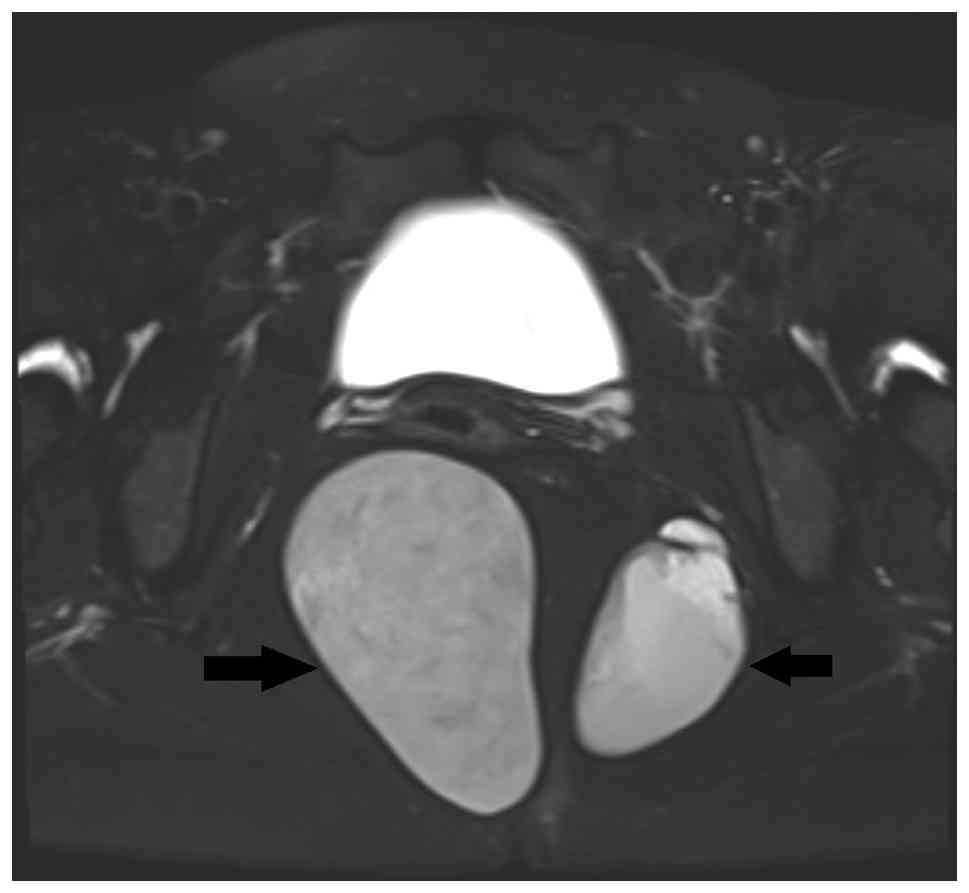

A 32-year-old previously healthy female presented to the First People's Hospital of Xiaoshan District (Hangzhou, China) in September 2024 with unexplained abdominal pain, which was the first occurrence of such symptoms within the preceding 2 months. The patient exhibited no signs of intestinal dysfunction or symptoms indicative of urinary tract irritation. Notably, a digital rectal examination revealed a solid, fixed mass located on the posterolateral wall of the rectum. Gynecological ultrasound prior to surgery revealed two unevenly strong echo masses in the pelvic cavity that were located posterior to the cervix and lateral to the rectum (Fig. 1). The larger mass measured ~8.0x6.5x6.1 cm, whereas the second largest measured ~6.4x6.0x4.8 cm. Both masses had clear boundaries and regular shapes, with no obvious blood flow signals detected. MRI revealed two abnormal signal shadows in the perirectal and bilateral rectal fossa. The larger shadow measured ~53x81 mm, with a clear boundary and smooth edges. The cyst fluid exhibited low signal intensity on T1-weighted imaging (T1WI), and high signal intensity on T2WI (Fig. 2). The internal signal was slightly mixed, with pronounced high signal intensity on diffusion-weighted imaging (DWI) and low signal intensity on apparent diffusion coefficient (ADC) mapping. No enhancement within the cyst was observed after contrast administration. A circular low signal intensity was visible on T2WI in the cyst wall, which was moderately enhanced after contrast administration.

Magnetic resonance imaging T2-weighted

imaging scan showing two cystic masses characterized by

well-defined boundaries and smooth margins. The internal

composition exhibited slightly heterogeneous signals, predominantly

hyperintense, accompanied by annular hypointense signals within the

cystic walls. Arrows indicate the presacral tumors.

Figure 2

Magnetic resonance imaging T2-weighted imaging scan showing two cystic masses characterized by well-defined boundaries and smooth margins. The internal composition exhibited slightly heterogeneous signals, predominantly hyperintense, accompanied by annular hypointense signals within the cystic walls. Arrows indicate the presacral tumors.